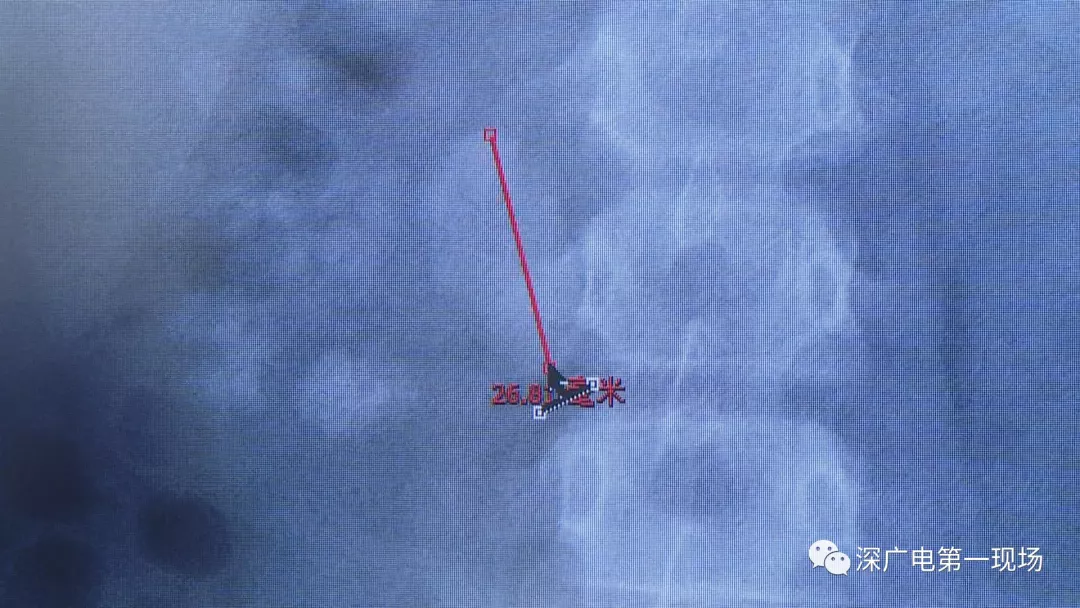

小軒這種情況,其中,最大的結(jié)石長(zhǎng)約2.7厘米,寬約1.7厘米,體積堪比鵪鶉蛋,不但造成了尿路堵塞,還導(dǎo)致了右腎中度積水。